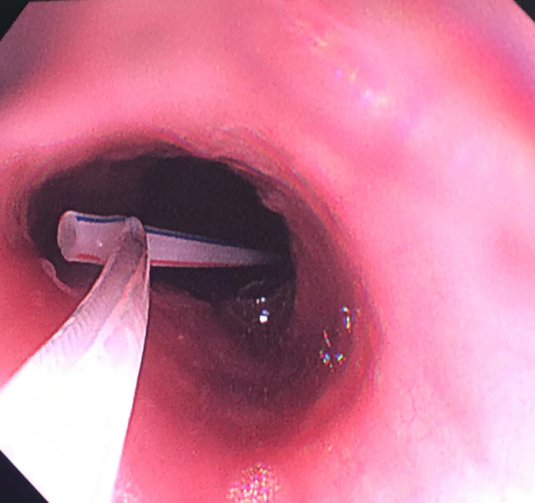

- 内镜下的骨片 -

处于休息时间的儿科李中跃主任医师,在了解该患儿情况后,立即从家中驱车赶至医院。

- 顺利取出的骨片 -

在急诊科、麻醉科及手术室医护人员的多科协助下,李中跃主任医师将嵌顿于食管上的 2 cm 尖锐骨片,用鼠齿钳夹住并运用一定手法后顺利取出。